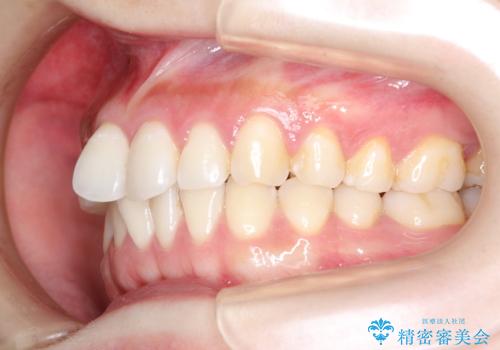

初診時の歯並びの状態としては、上下にガタガタがある状態であり、特に上の前歯(左上1番)の捻じれを最も気にしていらっしゃいました。

口元の位置も悪くなくスペース必要量も軽度であったため、非抜歯/マウスピース矯正にて治療を行いました。

前歯の捻じれを改善するためにスペースを作る必要があり、前歯の歯の間を削って簡単に直す方法もありますが、奥歯のズレが認められたため、大臼歯後方のスペースを利用し、根本的な原因からしっかりと治療を行いました。